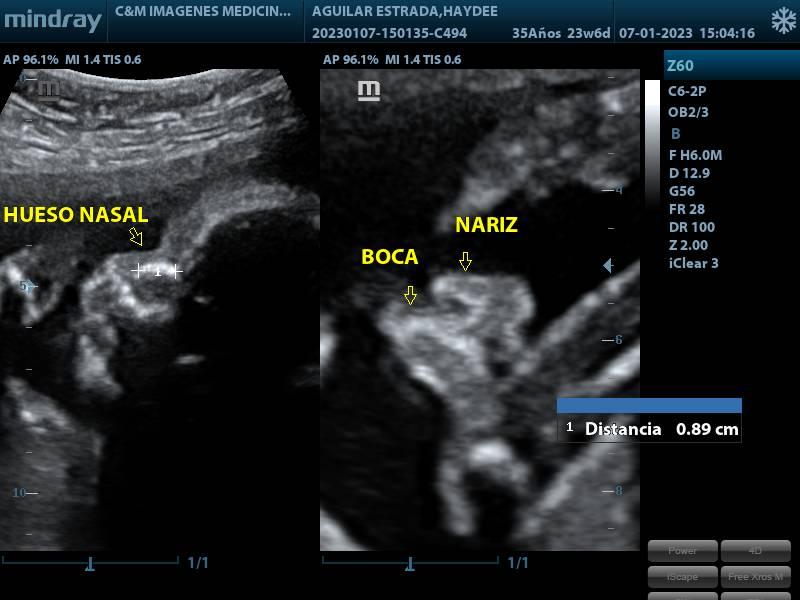

SCREENING DEL SEGUNDO TRIMESTRE

SERVICIOSCREENING DEL SEGUNDO TRIMESTRE

PRESENTACIÓNECOGRAFIA

CONDICIÓNINDICACIONES: SE REALIZA ENTRE LAS 20 Y 24 SEMANAS DE GESTACION.

TIEMPO40 MINUTOS

TIPO RESULTADOSIMAGENES ECOGRAFICAS

ESPECIFICACIONESSE ESTUDIA: BIOMETRIA FETAL DIAMETRO BIPARIETAL (DBP) CIRCUNFERENCIA CEFALICA (CC) CIRCUNFERENCIA ABDOMINAL (CA) LONGITUD DE FEMUR (LF) LONGITUD HUMERO (LH) SITUACION Y POSICION FETAL UBICACIÓN Y MADUREZ DE PLACENTA CANTIDAD DE LIQUIDO AMNIOTICO (ILA) SEMANAS DE GESTACION PESO FETAL SEXO FRECUENCIA CARDIACA FETAL (LCF) OBSERVACION MOVIIENTO FETAL ESTUDIO ANATOMICO FETAL ESTOMAGO, PULMONES, VEJIGA, RIÑONES EVALUACION DIAFRAGMA ESTUDIO CORAZON (4 CAMARAS CARDIACAS, VALVULAS, FLUJO SANGUINEO) CABEZA FETAL (CEREBELO, CSP, VENTRICULOS LATERALES, CISTERNA MAGNA, FOSA POSTERIOR, ETC) CARA FETAL (ORBITAS OCULARES, CRISTALINO, HUESO NASAL, LABIOS, NARIZ OBSERVACION COLUMNA VERTEBRAL Y EXTREMIDADES FLUJOMETRIA DOPPLER ARTERIAS UTERINAS (PREVENTOR PREECLAMPSIA) ARTERIA CEREBRAL MEDIA (ACM) ARTERIA UMBILICAL RELACION CEREBROPLACENTARIA.